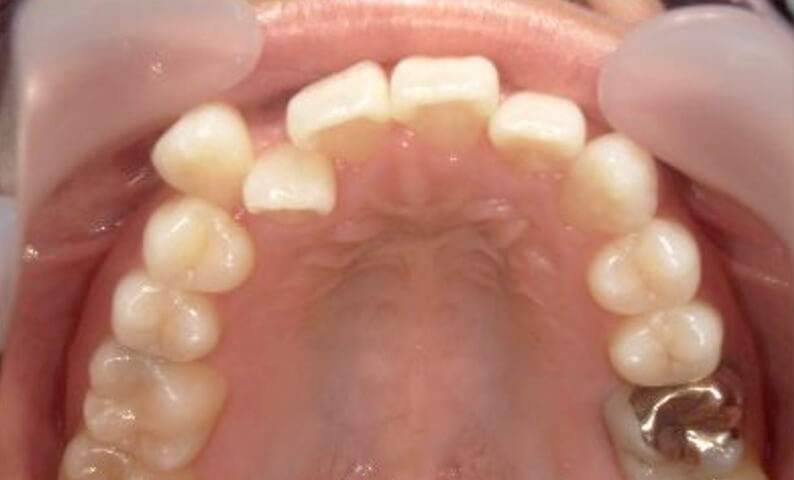

症例_002 下顎だけの部分矯正

治療期間:4ヶ月金額:30万円+税女性前歯のガタガタ下の前歯だけ

| Before | After |

|---|---|

|